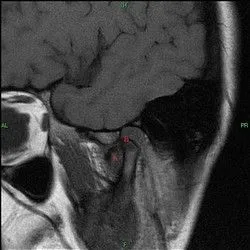

and will not pop back in place as you attempt to open. This limited opening is usually in the range of two finger widths between the anterior teeth. To the right is an MRI of a patient with a displaced disc that would not return to normal position upon opening, thus preventing the patient from opening fully. The MRI is labeled with an A next to the disc and a B in the position were the disc belongs.

If the disc is not repositioned into it's proper position within a reasonable amount of time, it can change shape making it impossible to ever return to it's normal position.